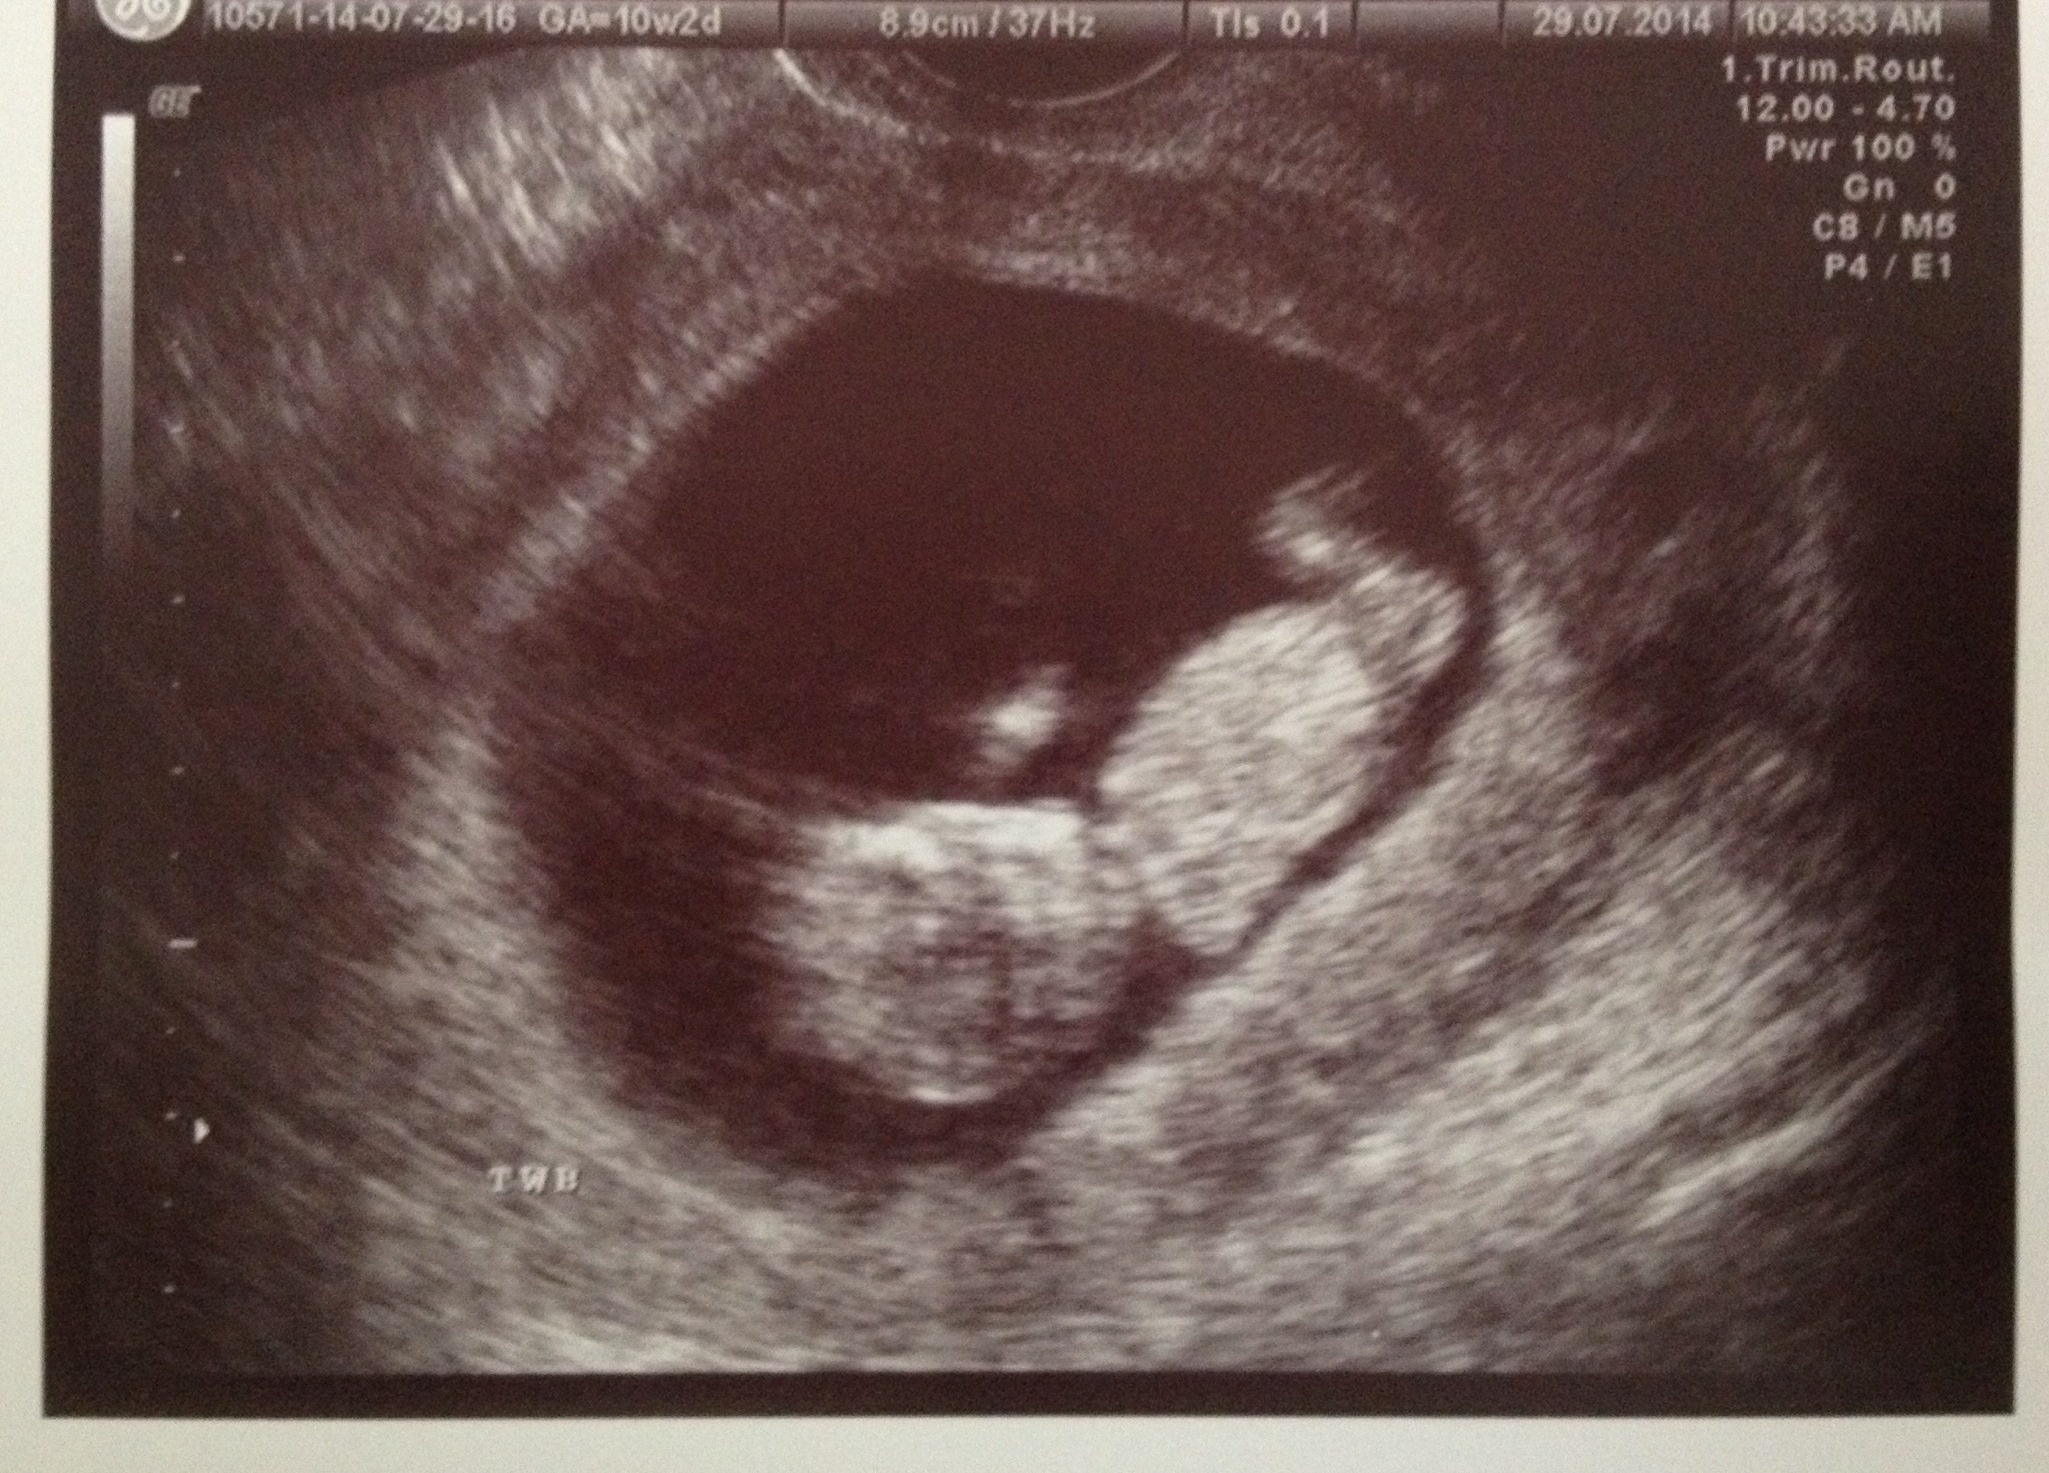

Ultrasound set for 2/17/14......TWINS! Twin A - HR 124 bpm; Twin B - HR 126 bpm

Final Ultrasound with RE 3/10/14 - Twin A - HR 176 bpm; Twin B - HR 177 bpm.